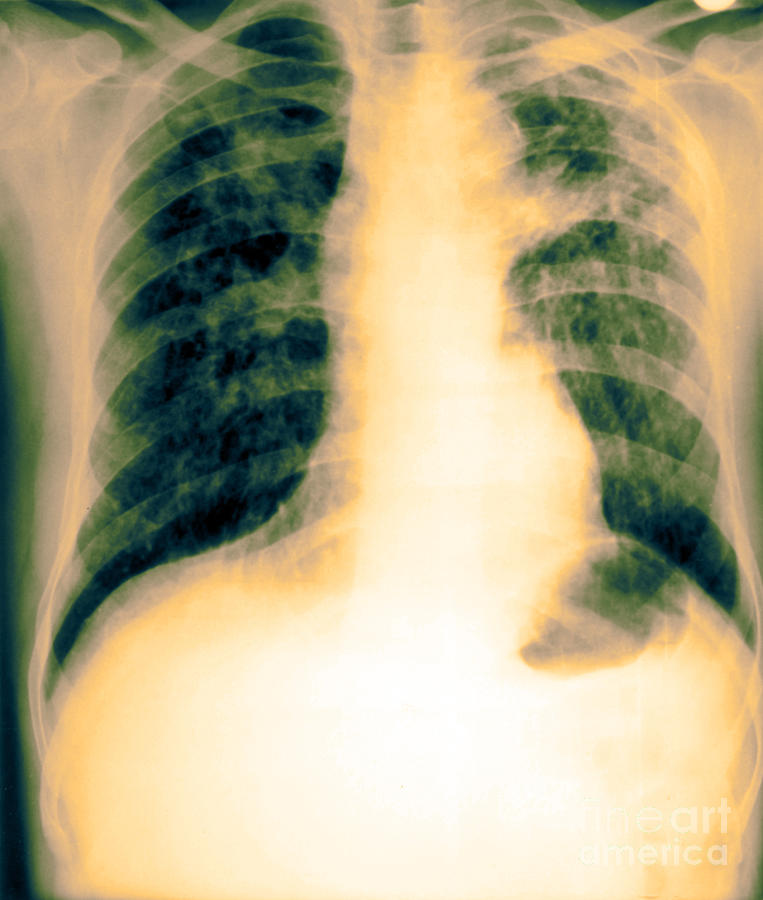

Xray Of Tuberculosis Photograph by Biophoto Associates Fine Art America